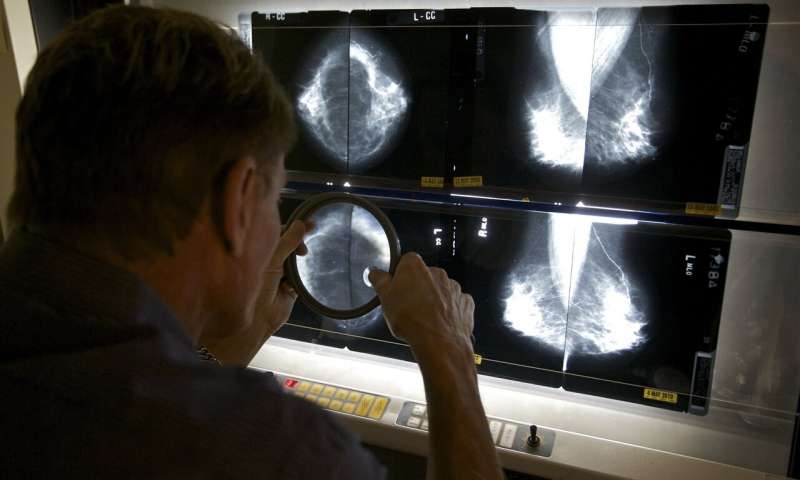

休斯顿MD安德森癌症中心的乳房专家詹妮弗·利顿(Jennifer Litton)博士说,该结果是激素使用者应遵循指南以定期进行乳房X线检查以检查癌症的另一个原因。

她说:“继续进行适当的筛查仍然很重要。”